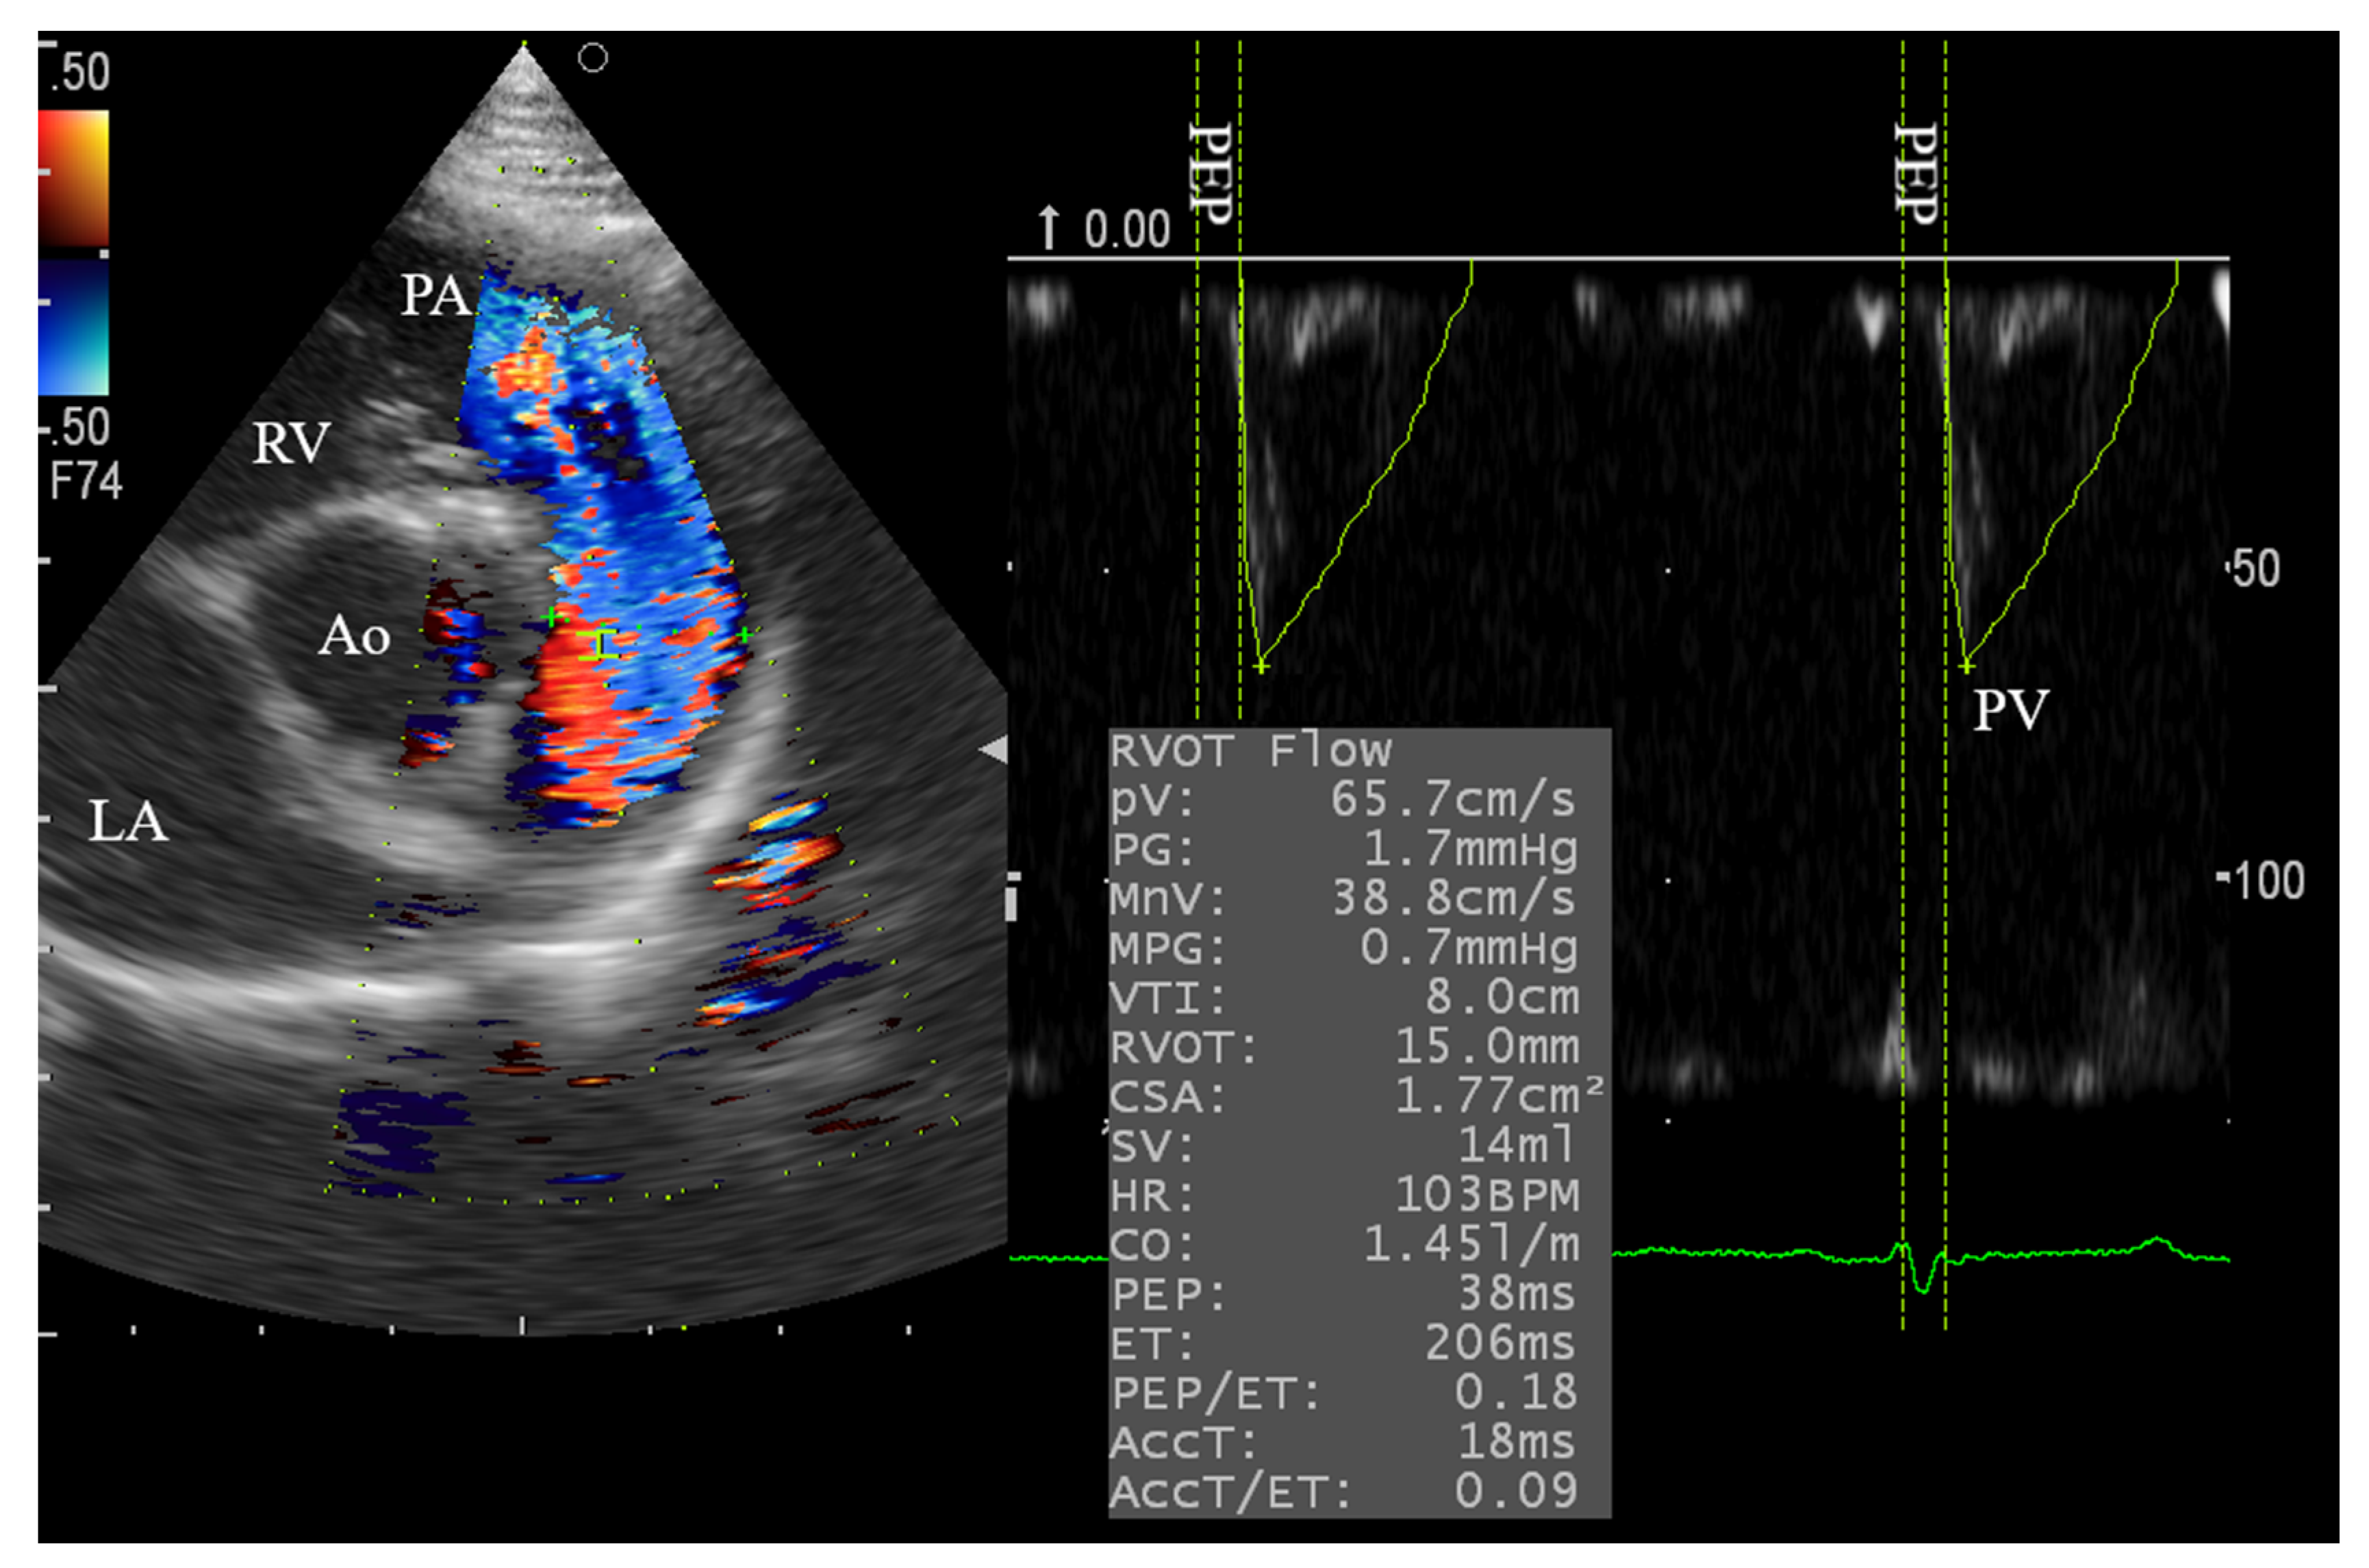

3.3. Right Side Echocardiography and the Effect of Xylazine Administration

| Pulmonary | PV | cm/s | 81.34 | 14.64 | 0.063 | ns | 17.99 |

| PG | mmHg | 2.561 | 0.574 | >0.10 | ns | 22.43 | |

| MnV | cm/s | 55.43 | 11.37 | >0.10 | ns | 20.51 | |

| MPG # | mmHg | 1.427 | 0.652 | 0.0021 | ** | 40.01 | |

| VTI | cm | 11.77 | 2.571 | >0.10 | ns | 21.85 | |

| RVOT | mm | 14.63 | 2.181 | >0.10 | ns | 14.91 | |

| CSA | cm2 | 1.721 | 0.495 | >0.10 | ns | 28.78 | |

| PEP | ms | 42.04 | 5.684 | >0.10 | ns | 13.52 | |

| ET | ms | 212.8 | 29.56 | >0.10 | ns | 13.89 | |

| PEP/ET # | 0.201 | 0.051 | 0.0001 | *** | 24.38 | ||

| ACCT | ms | 93.77 | 33.5 | >0.10 | ns | 35.73 | |

| ACCT/ET # | 0.427 | 0.138 | 0.016 | * | 32.19 | ||

| Pulmonary Doppler | ||||

| PV | cm/s | 85.4 ± 4.0 | 70.7 ± 3.7 | 0.04 * |

| PG | mmHg | 3.0 ± 0.3 | 2.1 ± 0.2 | 0.04 * |

| MnV | cm/s | 56.2 ± 2.8 | 46.0 ± 3.3 | 0.07 |

| MPG # | mmHg | 1.4 ± 0.1 | 1.0 ± 0.1 | 0.04 * |

| VTI | cm | 11.3 ± 0.5 | 11.0 ± 1.5 | 0.88 |

| RVOT | mm | 14.6 ± 0.5 | 15.7 ± 0.6 | 0.17 |

| CSA | cm * | 1.7 ± 0.1 | 2.0 ± 0.1 | 0.15 |

| PEP | ms | 42.6 ± 3.3 | 45.0 ± 2.7 | 0.49 |

| ET | ms | 205.2 ± 12.6 | 234.2 ± 22.4 | 0.32 |

| PEP/ET # | 0.2 ± 0.0 | ±0.2 ± 0.0 | 0.45 | |

| ACCT | cm/s | 72.5 ± 11.8 | 92.3 ± 12.9 | 0.35 |

| ACCT/ET # | 0.3 ± 0.0 | 0.4 ± 0.0 | 0.18 | |